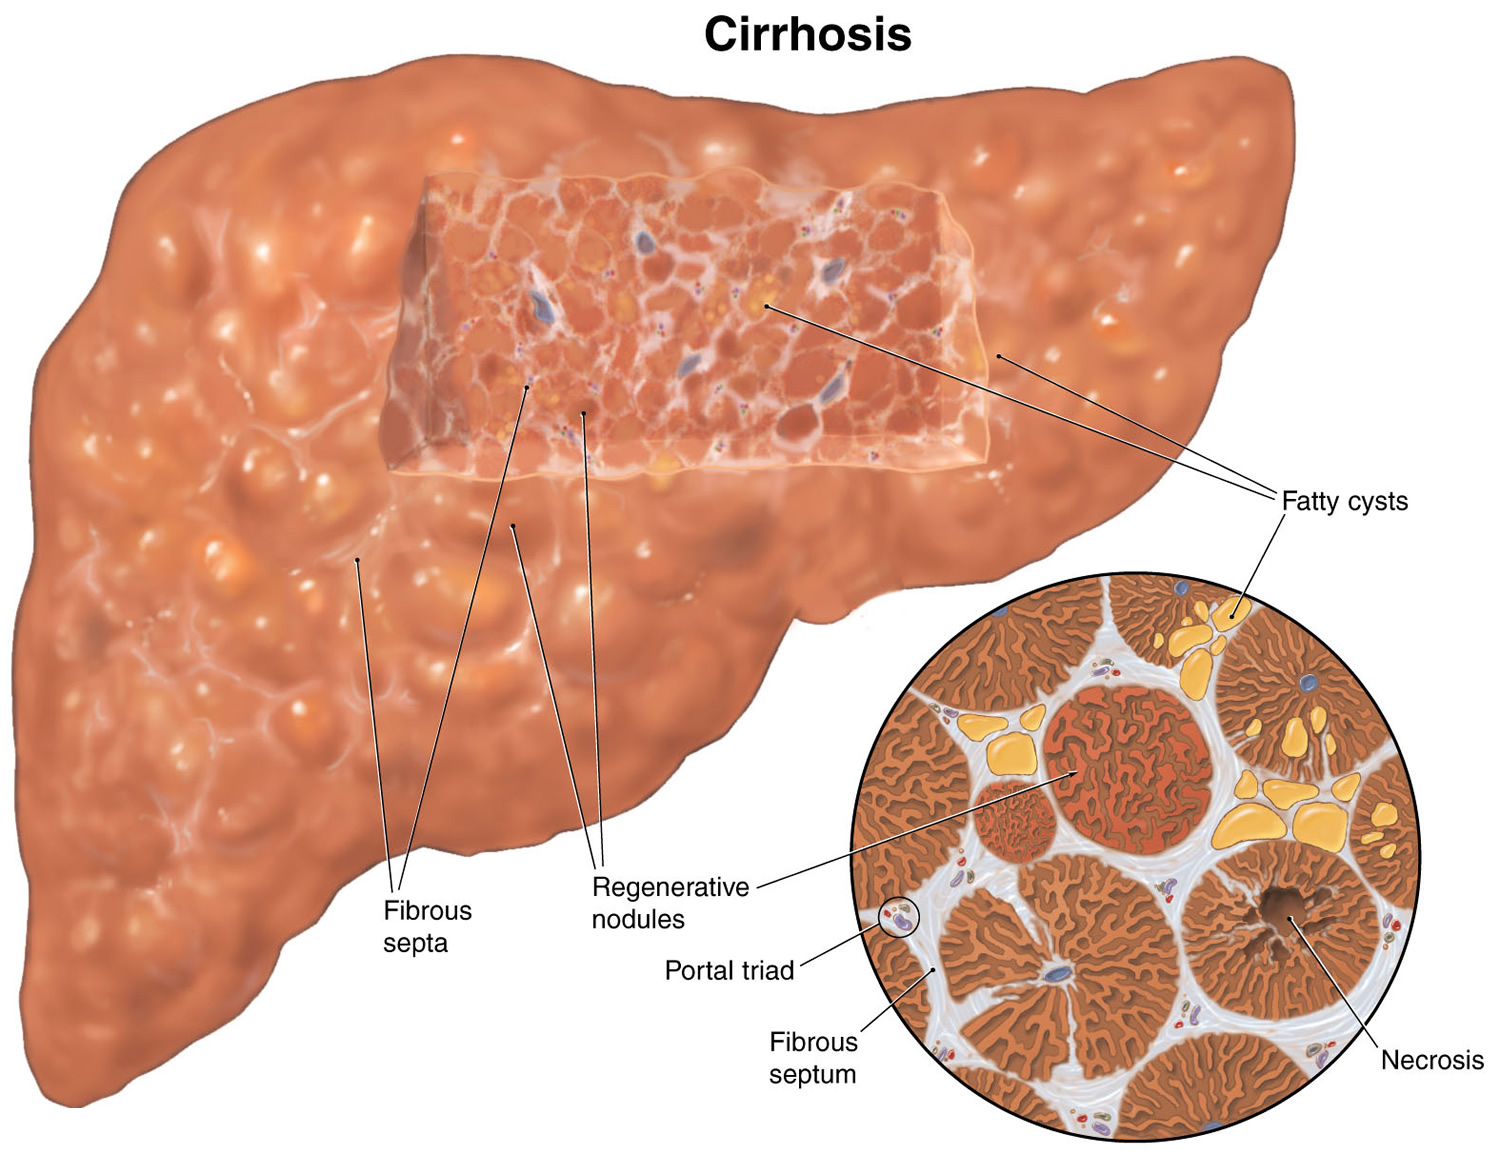

Cirrhosis Of The Liver Symptoms Diagnosis Survival Rate And Treatment